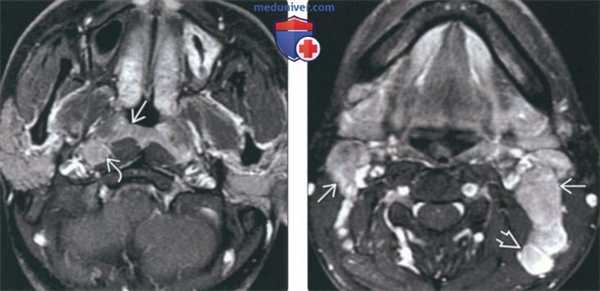

(Слева) На аксиальной МРТ (Т1 ВИ С+ FS) у мужчины 26 лет из Азии с объемными образованиями шеи определяется слегка асимметричное мягкотканое включение в слизистой оболочке носоглотки без признаков инфильтрации превертебральных мышц. Визуализируется увеличенный заглоточный лимфоузел.

(Справа) На аксиальной МРТ (Т1 ВИ С+ FS) у этого же пациента визуализируются увеличенные лимфоузлы II и V уровня, в которых были выявлены метастазы недифференцированного неороговевающего рака, ВЭБ(+). Т1N2, III стадия заболевания.

(Справа) На аксиальной МРТ (Т1 С+ FS) у этого же пациента определяется РНГ в левом боковом кармане носоглотки с распространением в окологлоточное пространство. Хорошо визуализируются вторично измененные контралатеральные заглоточные лимфоузлы и ипсилатеральные лимфоузлы IIВ уровня. T3N2, III стадия.